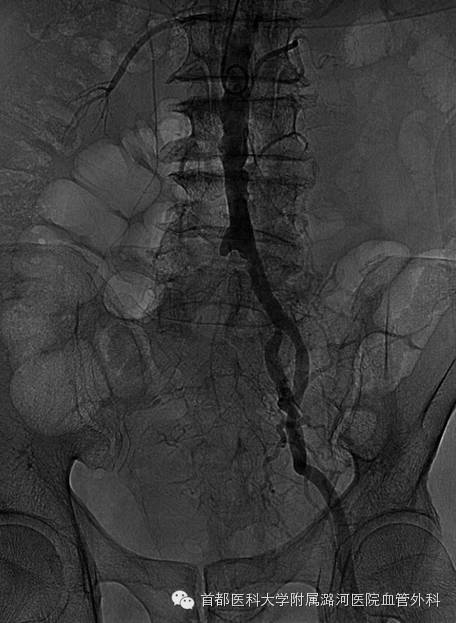

为了验证术前诊断的准确性,左侧肱动脉穿刺,腹主动脉下缘置入猪尾导管造影显示:

右侧髂总动脉起始段至髂外动脉末端全程闭塞

导丝通过右侧髂总动脉起始段受阻,其余导丝无阻力通过。

于右侧髂动脉内低压造影显示右侧髂总末端至髂外动脉全程充盈缺损。

证实右侧髂总动脉起始端重度狭窄基础上继发血栓形成;以血栓为主。